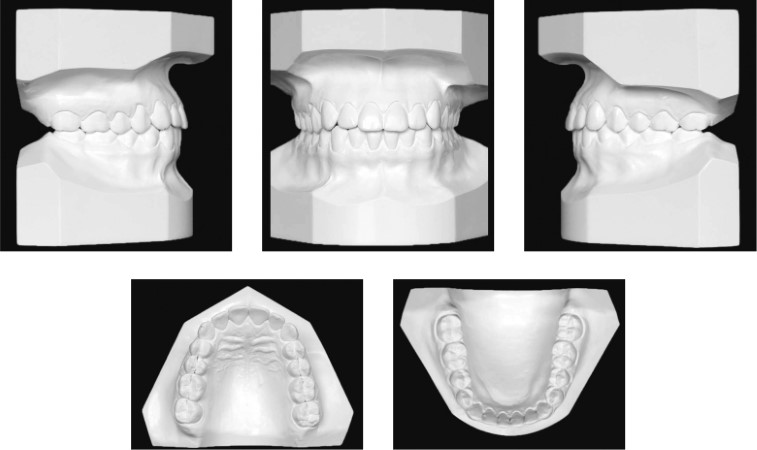

Modelos de Estudio